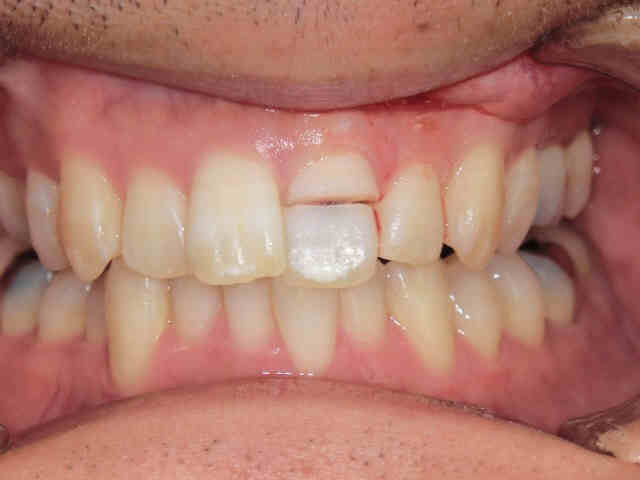

治療後には、見た目や機能面で自然に近い仕上がりを実現できたことから、患者様にもご満足いただけた様子でした。

下の写真は、治療完了後の状態です。